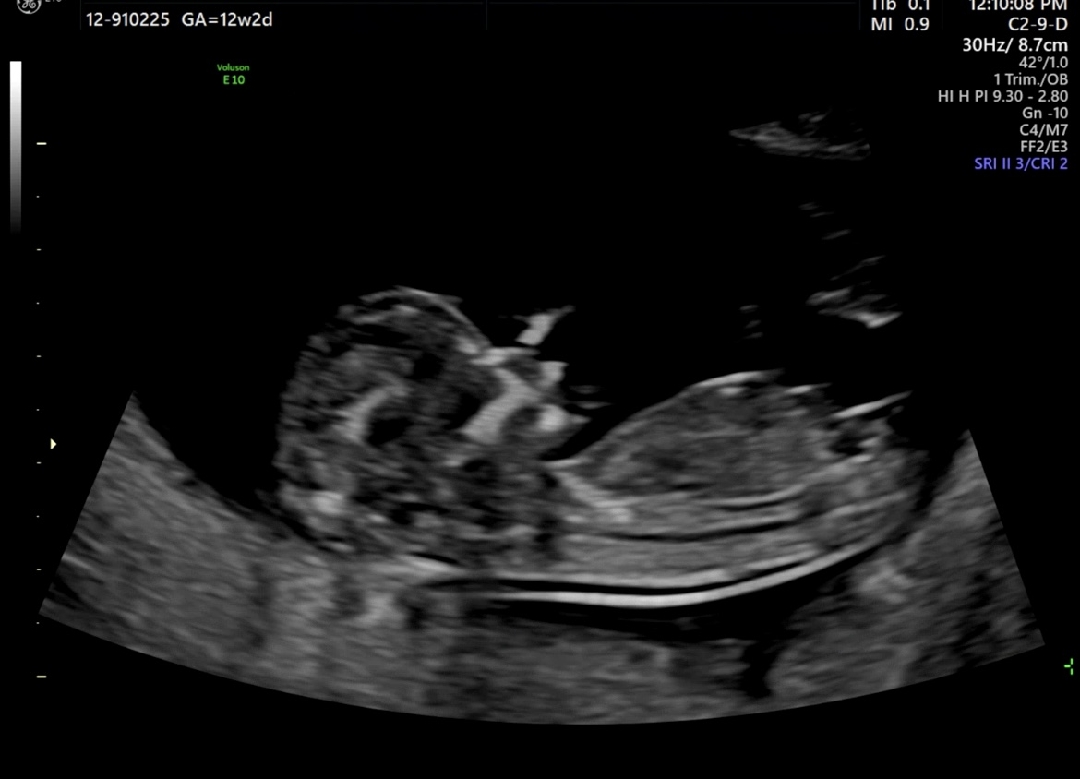

[12주차]각도법 봐주세요!

12주차 각도법 봐주세요~!